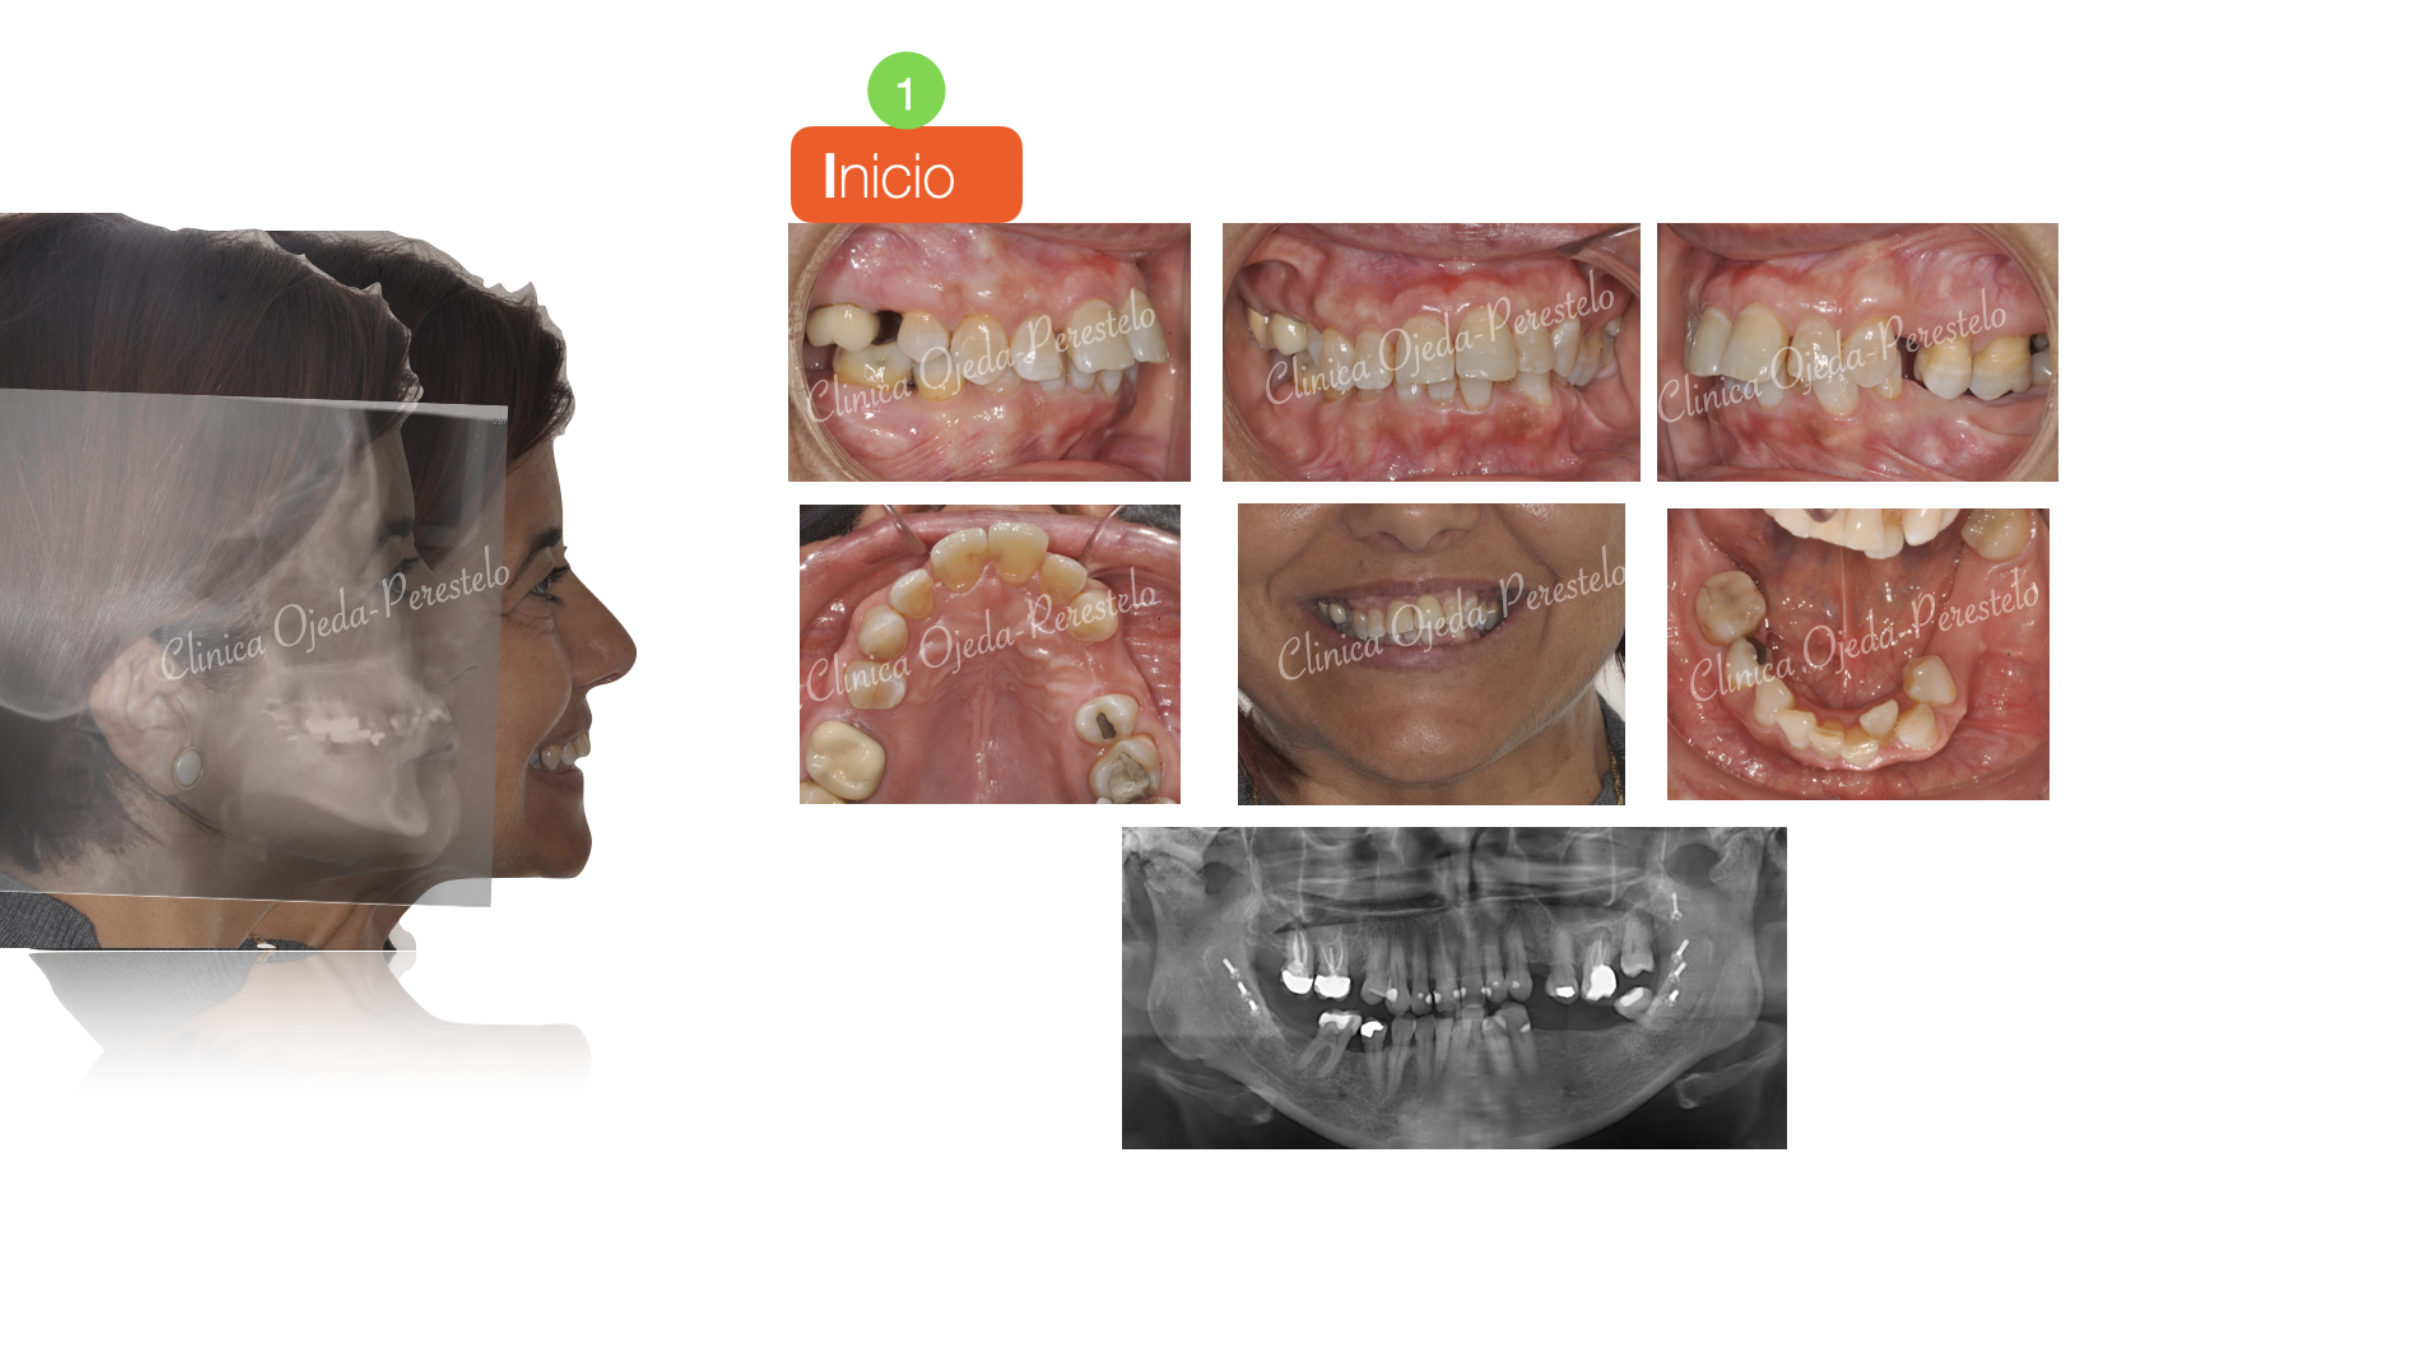

La rehabilitación oral completa en los pacientes adultos requiere en algunas ocasiones de planes de tratamiento bien coordinados entre las diferentes disciplinas odontológicas. Presentamos un caso de alta complejidad de una paciente que había sido intervenida de una cirugía de Avance Mandibular con remodelamiento condilar.

El objetivo de la etapa ortodóncica no era otro que alinear y nivelar sus arcadas dentarias y adecuar los espacios para la colocación (futura) de implantes y pónticos. Al tratarse de una paciente con limitación de apertura y el plano Maxilar inclinado y descendido en el lado derecho, se decidió combinar alineadores transparentes (Sistema Invisalign) con Microtornillos estratégicamente colocados.